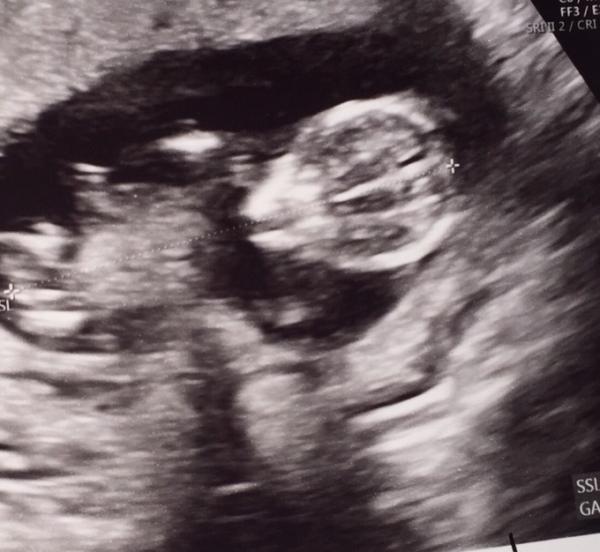

Hallo ihr lieben. Ich war ja heute zum 1. großen Screening beim Arzt. Also erst Vorsorge bei meiner Hebamme und dann zum Doc. Was soll ich sagen, es war toll. Der Wurm hat sich Prächtig entwickelt. Etwas über 6cm groß, NF unauffällig, Bauch und Rücken geschlossen. Und er hat fleißig geturnt. Mein Arzt hat mich auch ein paar Tage vorgestuft, bin jetzt 12+3. Blut für den Fetalis Test wurde auch abgenommen. Ergebnis kommt in einer Woche. Geschlecht erfahren wir ab 14+0. Bin glücklich

Bild zu Arzttermin - Forum für Januar - Mamis